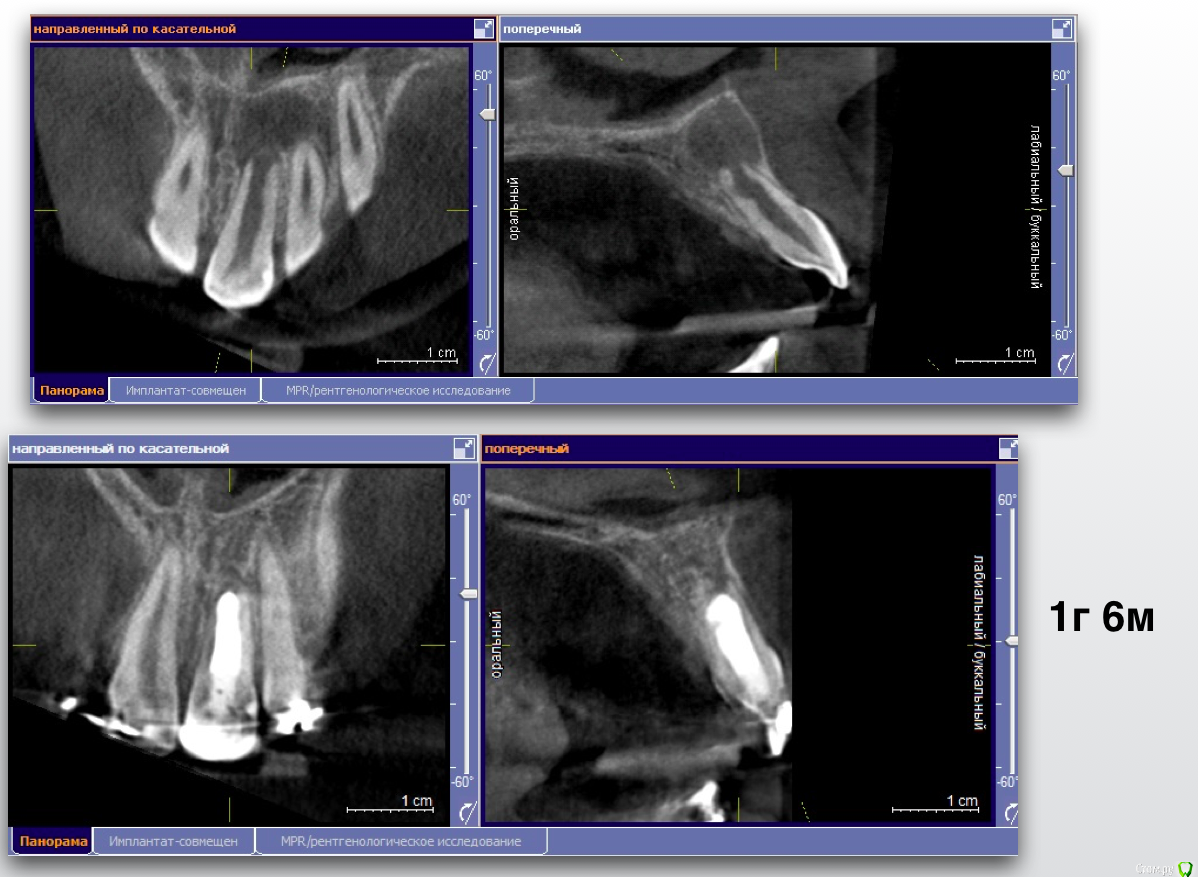

Гарриевич Опубликовано 5 февраля, 2019 Поделиться Опубликовано 5 февраля, 2019 Хочу рассказать одну маленькую историю об одной маленькой девочке, которая произошла не так давно, чтобы ее забыть, но и достаточно давно, чтобы убедиться в её хорошем конце.Утро у нас в клинике всегда начинается с пятиминутки, это время когда мы обсуждаем записанных на день пациентов и планируем лечение... то есть так должно быть, а по правде мы тратим эти 15 минут на обсуждение почему я опоздал, почему снова небритый и где вкуснее готовят кофе)Вообще душевный коллектив это здорово.Так вот на одной из пятиминуток главврач показал мне КТ 11-летней девочки с «кистой» верхнего центрального резца. До нас родители обращались в один большой московский Стоматологический ВУЗ и там и рекомендовали зуб удалить (киста же!), брекеты поставить, а после снятия брекетов и до 21 года ходить со съёмным протезом... у меня все... как вам план?Но есть стоматологи который читают современные книжки и есть пациенты которые читают, в правильных дозах, интернеты, и когда родители пришли к нам и услышали, что зуб не только не надо удалять, но ещё и можно вылечить, то обрадовались и остались лечиться. Всем пациентам довершим мне лечение зубов с «кистами»: спасибо! Прикладываю все усилия, чтобы каждый день это доверие оправдывать. Хорошего дня, Гарриевич. P.S. Разница между снимками 1,5 года 13 Ссылка на комментарий

Гарриевич Опубликовано 6 февраля, 2019 Автор Поделиться Опубликовано 6 февраля, 2019 Спасибо за кейс доктор , всегда приятно смотреть на борьбу со злом которая заканчивается победой "наших".. Расскажите немного о том какой природы была киста(диагноз так понимаю не гистологический) , и какими материалами работали в канале, заранее благодарю . спасибо)кистой я это называю исключительно в целях упрощения понимания пациентами. Конечно это банальный апикальный периодонтит с внушительных размеров резорбциейв канале мта и гутта (горячая) с эпоксидкой Ссылка на комментарий

Гарриевич Опубликовано 6 февраля, 2019 Автор Поделиться Опубликовано 6 февраля, 2019 Зачет! До какого расширяли?там до меня уже все само расширено былотолько ирригация с активацией 1 Ссылка на комментарий